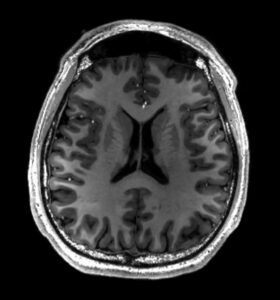

Neuroscience Perspective: Can Electromagnetic Energy Affect the Brain?

Neuroscience research confirms that electromagnetic fields can influence neural activity under specific laboratory conditions.

However, large-scale real-world neurological disruption through covert electromagnetic targeting remains scientifically unproven.